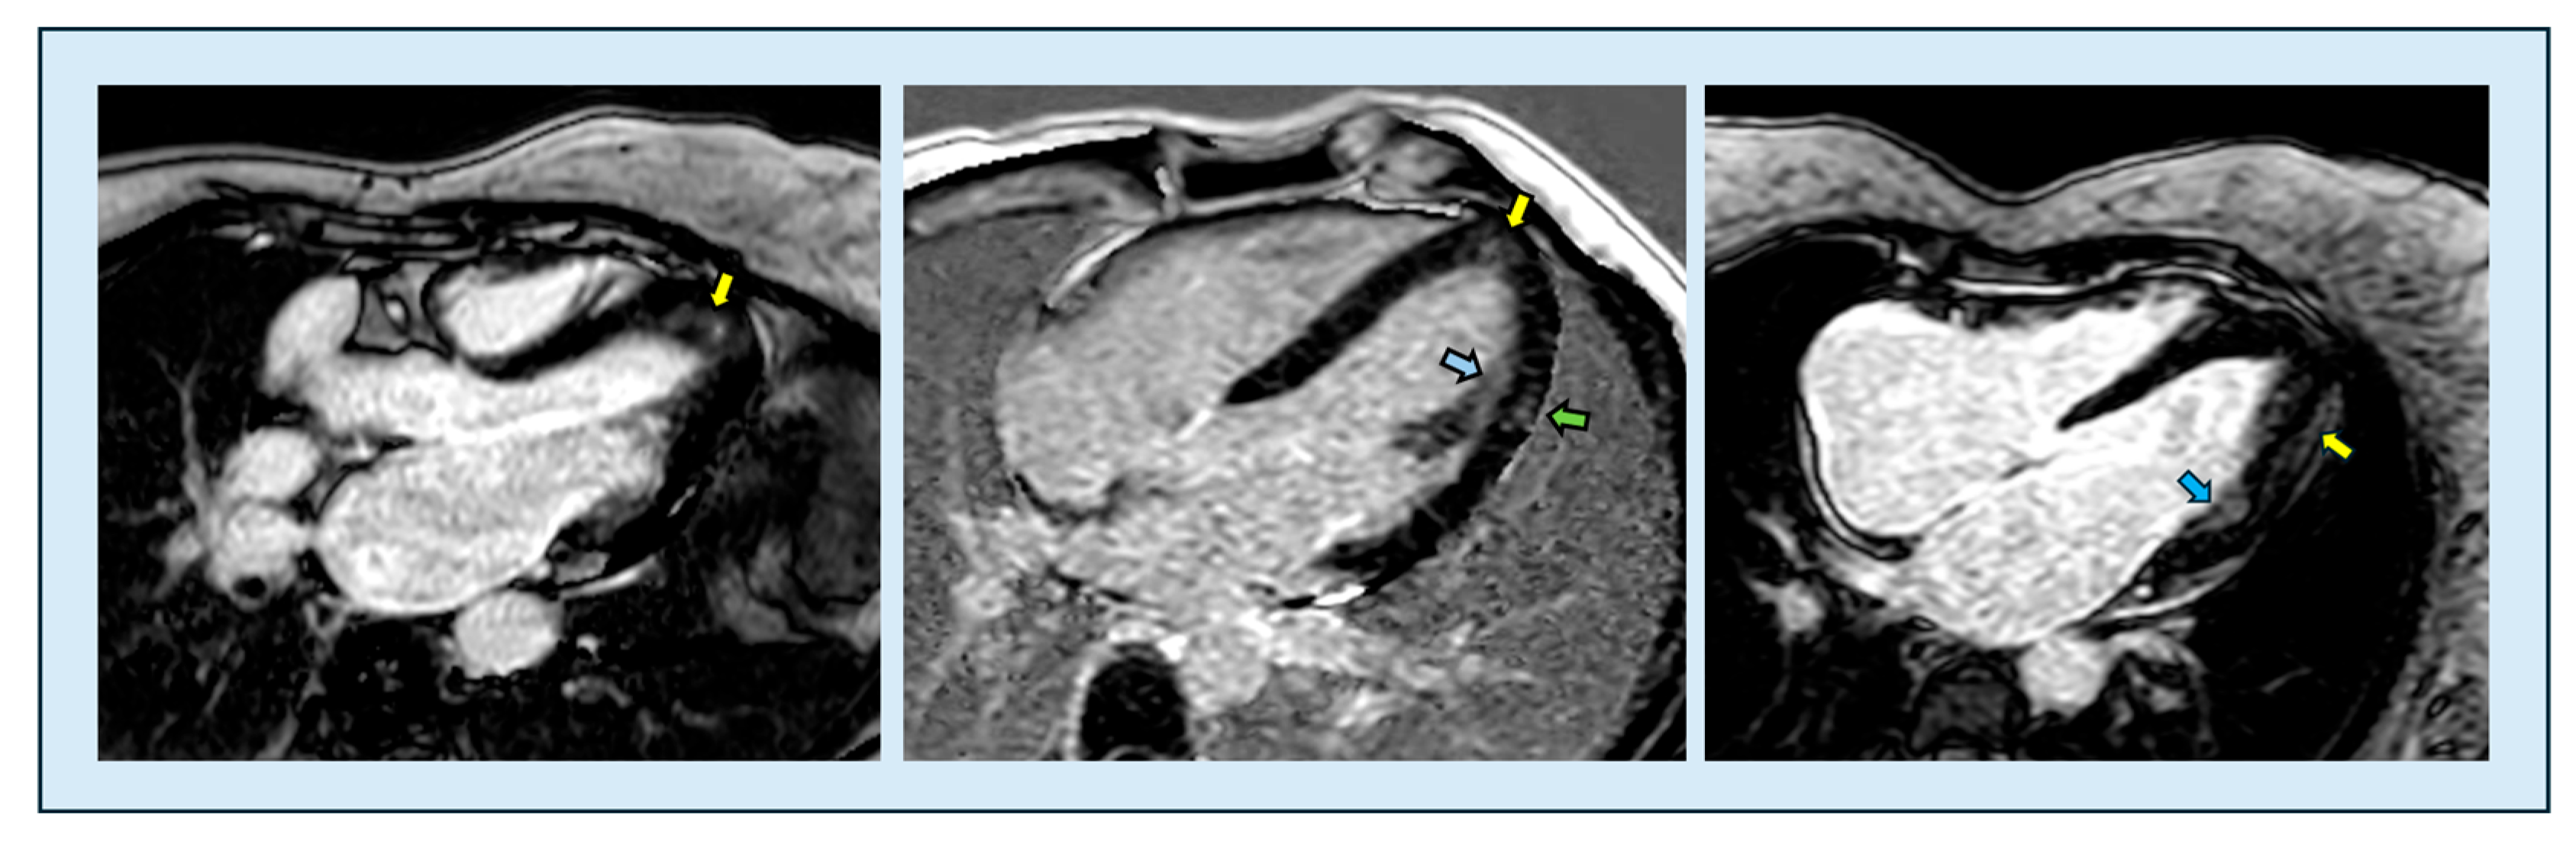

6.1. Cine-MR and Morphology

6.3.3. Late Gadolinium Enhancement